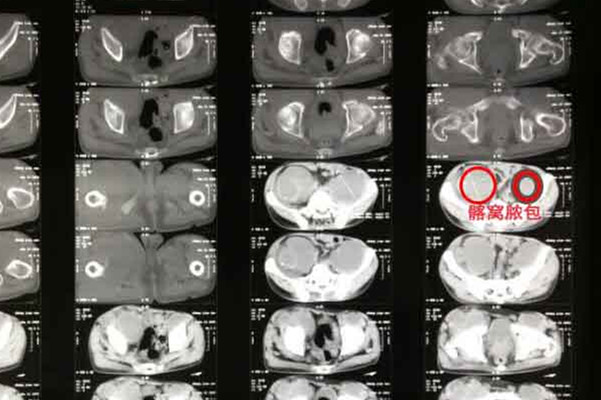

如果说骨结核复发病情严重,可行手术治疗,手术包括脓肿切开排脓术、病灶清除术、矫正畸形的截骨术、改善关节功能的关节成形术、增强脊柱稳定性的脊柱内固定术等。